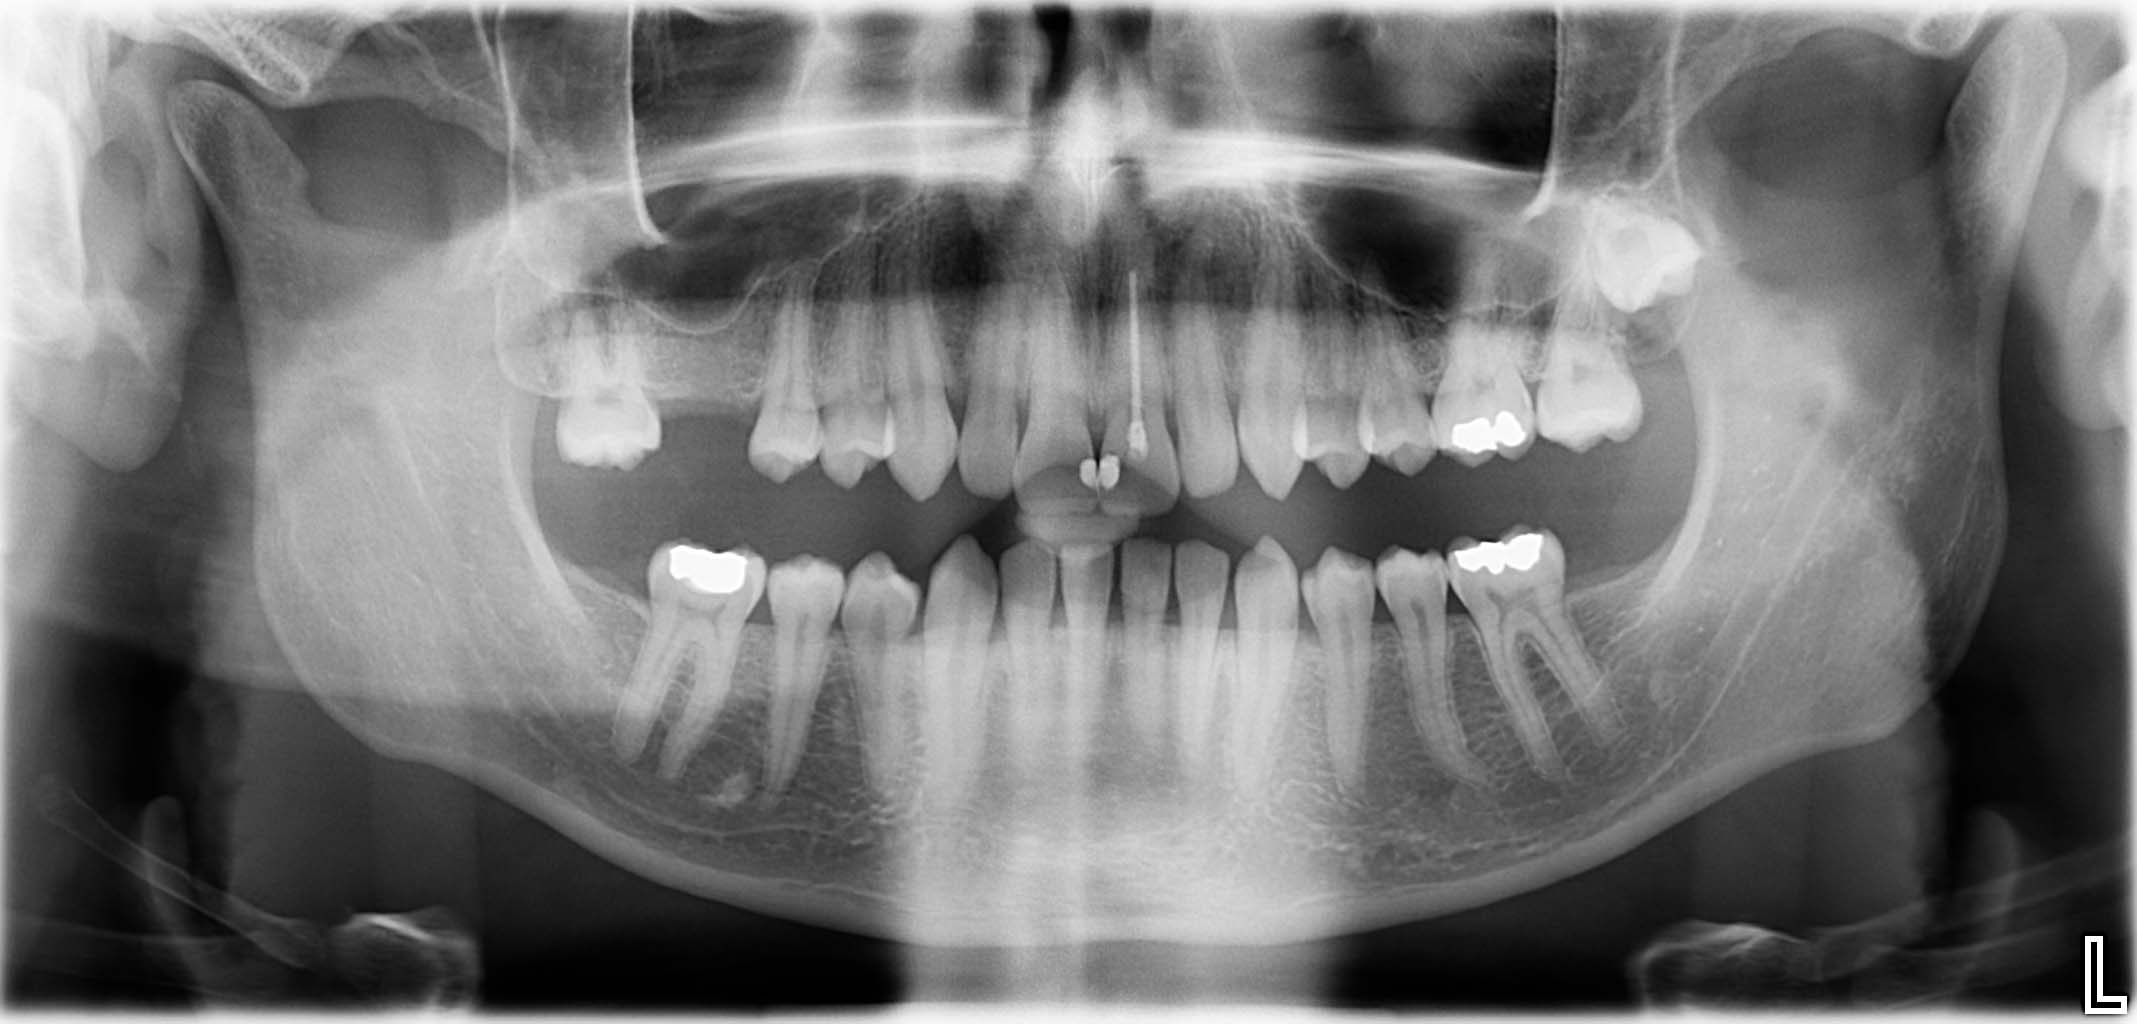

Ausgangssituation: Zahn 36 mit apikaler Beherdung, nicht erhaltungswürdig

Erfolgreich implantierte Patientenfälle (klinische Fotos)